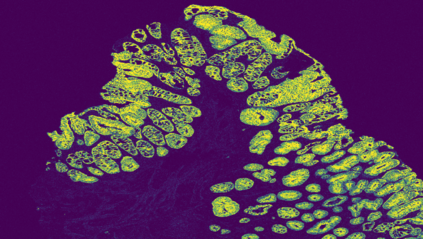

The usage of chemical imaging technologies is becoming a routine accompaniment to traditional methods in pathology. Significant technological advances have developed these next generation techniques to provide rich, spatially resolved, multidimensional chemical images. The rise of digital pathology has significantly enhanced the synergy of these imaging modalities with optical microscopy and immunohistochemistry, enhancing our understanding of the biological mechanisms and progression of diseases. Techniques such as imaging mass cytometry provide labelled multidimensional (multiplex) images of specific components used in conjunction with digital pathology techniques. These powerful techniques generate a wealth of high dimensional data that create significant challenges in data analysis. Unsupervised methods such as clustering are an attractive way to analyse these data, however, they require the selection of parameters such as the number of clusters. Here we propose a methodology to estimate the number of clusters in an automatic data-driven manner using a deep sparse autoencoder to embed the data into a lower dimensional space. We compute the density of regions in the embedded space, the majority of which are empty, enabling the high density regions to be detected as outliers and provide an estimate for the number of clusters. This framework provides a fully unsupervised and data-driven method to analyse multidimensional data. In this work we demonstrate our method using 45 multiplex imaging mass cytometry datasets. Moreover, our model is trained using only one of the datasets and the learned embedding is applied to the remaining 44 images providing an efficient process for data analysis. Finally, we demonstrate the high computational efficiency of our method which is two orders of magnitude faster than estimating via computing the sum squared distances as a function of cluster number.